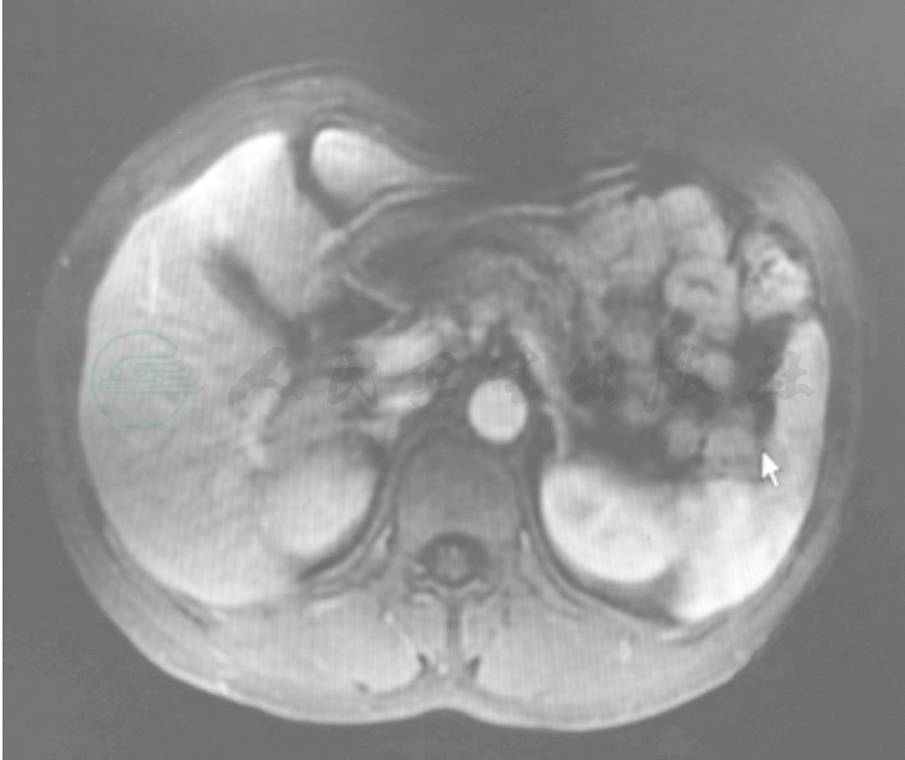

影像学检查:胰腺增强MRI:胰颈体部占位,胰腺癌伴腹膜后侵犯可能大,腹膜后淋巴结肿大(图1~图4)。

图2 T2WI图(箭头所指为肿块位置)